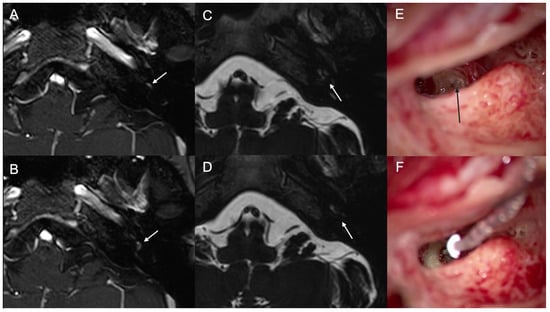

3.1. Case 1